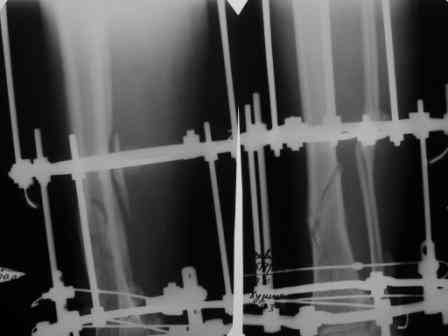

> июня 2006г авф. На сегодня - состояние консолидации представлено на

> рентгенограммах. Имеется ли целесообразность реостеосинтеза

> интрамедуллярным гвоздем?

Если не предполагается аппарат снять в ближайшие дни/недели, мы бы заштифтовали. Если клинически нет воспаления тканей у спиц.

на мой взгляд, консолидация достаточна для проведения пробы в аппарате, а ось вполне удовлетворительна.

по результатам пробы-остеосинтез ( или нет)

Антон, сделано-то ведь оччень не плохо. Что побуждает говорить о реостеосинтезе? Сроки? А Вы клиническую пробу(покачивание при раслабленных стержнях проводили? Мне кажется, что консолидация неплохая. Можно снять аппарат и 3 - 4 недели в У-образной лонгете. Обычно очень хорошая мозоль появляется.